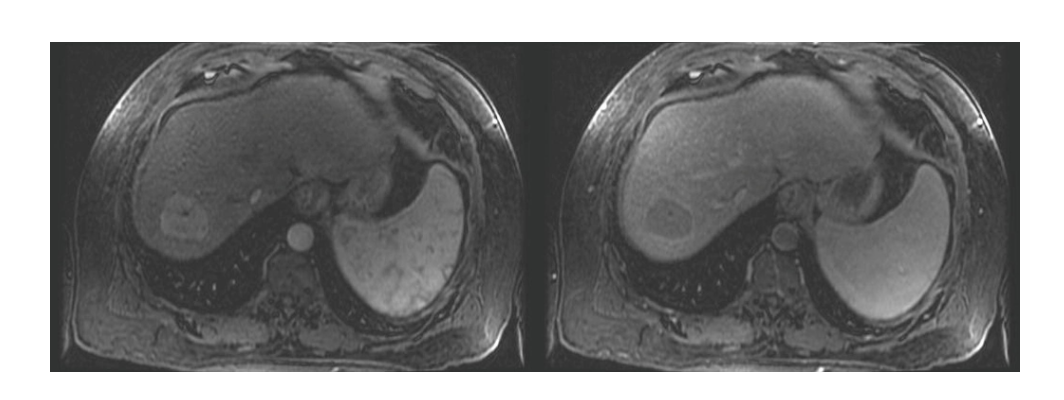

HCC imaging characteristics

arterial enhancement with venous washout